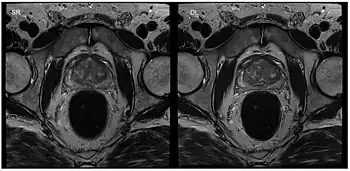

Although applications of real-time MRI cover a broad spectrum ranging from non-medical studies of turbulent flow[26] to the noninvasive monitoring of interventional (surgical) procedures, the most important application making use of the new capabilities is cardiovascular imaging.[1] Previous cardiac MR (CMR) used cine techniques to capture the periodic motion of the heart. However, this is not feasible for patients with arrhythmia, where the cardiac cycle is unpredictable.[27] With the new method it is possible to obtain movies of the beating heart in real time with up to 50 frames per second during free breathing and without the need for a synchronization to the electrocardiogram.[28] A study performed by Laubrock et al.[27] demonstrated that RT-MRI produced higher quality images with a higher SNR than cine CMR with a bSSFP sequence and radial k-space sampling. RT-MRI also removes the need for breath-holding while imaging, leading to a more comfortable experience for the patient as well.[27]